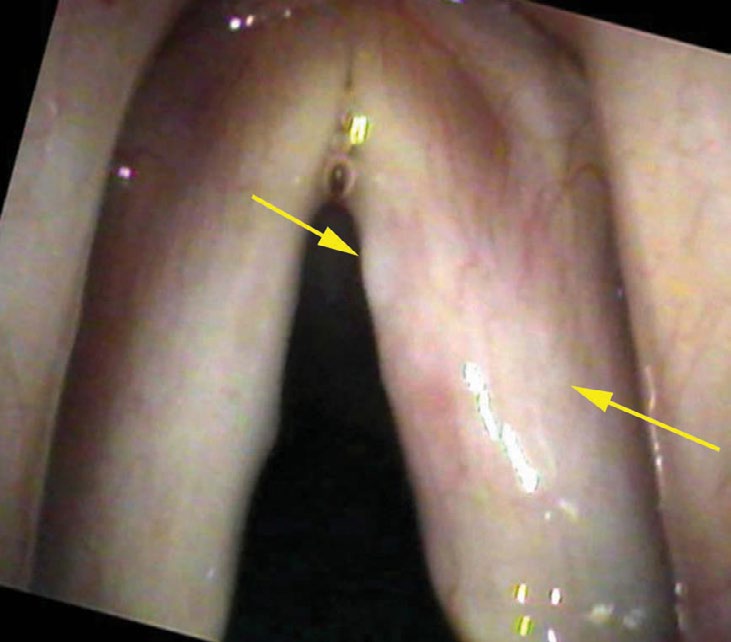

If we stop and search this close-up view for a time, we will begin to perceive that all of the vessels dim in the central portion of the vocal cord. They are actually diving under a thin film of white. Because the vocal cord itself is white, a white film on the surface (white on white) is not easily discernible. But if we concentrate on the vessels, we can see a distinct curving line where the vessels fade or disappear as they traverse the central portion of the vocal cord.

I make a diagnosis of fungal laryngitis since I perceive a whiteness and the typical throat fungus is Candida albicans, which is white. Fungus growing on the vocal cords would also stimulate increased blood flow or inflammation. The patient is on a steroid spray that, while very good for the prevention of asthma, will encourage the overgrowth of the normal fungal flora in the mouth and throat (also known as thrush).

There are more blatant examples of fungal infections. A suppressed immune system from treatments such as chemotherapy or systemic steroids for a prolonged period can lead to bright white, fuzzy patches growing all over the larynx and even the rest of the throat. I have also seen a few patients on steroid inhalers where the layers of fungus build up to the point that the lesion resembles a cancer.

- The key finding is a thin white film on the surface of the vocal cords that partially obscures the blood vessels beneath — visible only on very close inspection, often within one millimeter of the cord.